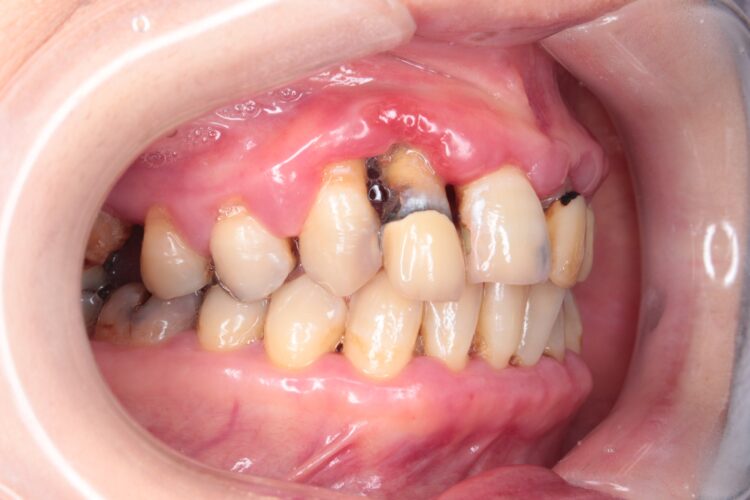

歯周病治療をスタートされた方の経過をご紹介します。

前歯がグラグラしてきたことを切っ掛けに受診されました。

治療に対して、可能な限り歯を残す事と、痛くない事を希望されています。

精密検査の結果、グラグラしている歯に重大な骨の喪失があることから、

どの程度保存出来るか不明であることが解りました。

また、歯ぐきも全体的にぷっくりと腫れており、他の歯にも動揺が出ていました。